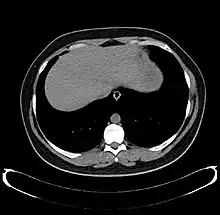

Axial CT image showing anomalous hepatic veins coursing on the liver's subcapsular anterior surface[66]

Maximum intensity projection (MIP) CT image as viewed anteriorly showing the anomalous hepatic veins coursing on the anterior surface of the liver

Lateral MIP view in the same patient as previous image

A CT scan in which the liver and portal vein are shown